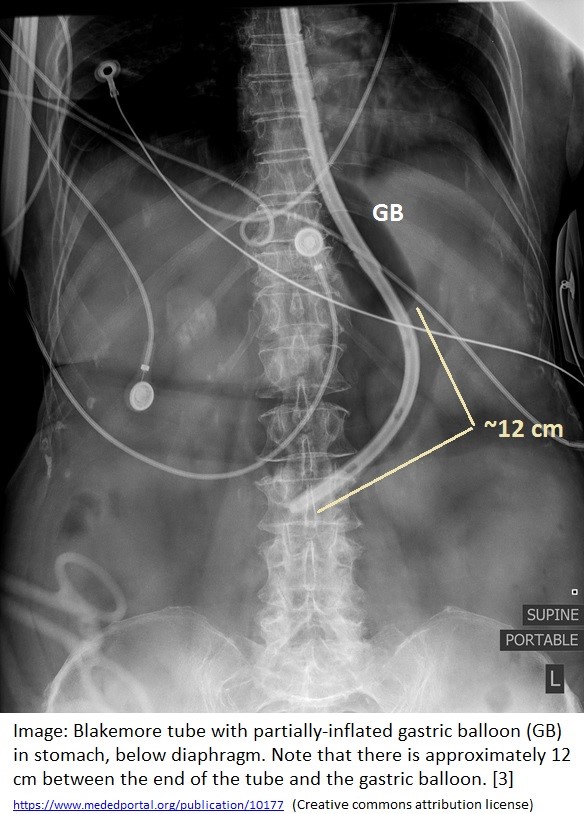

- Radiographic image showing GEBT placement [3]